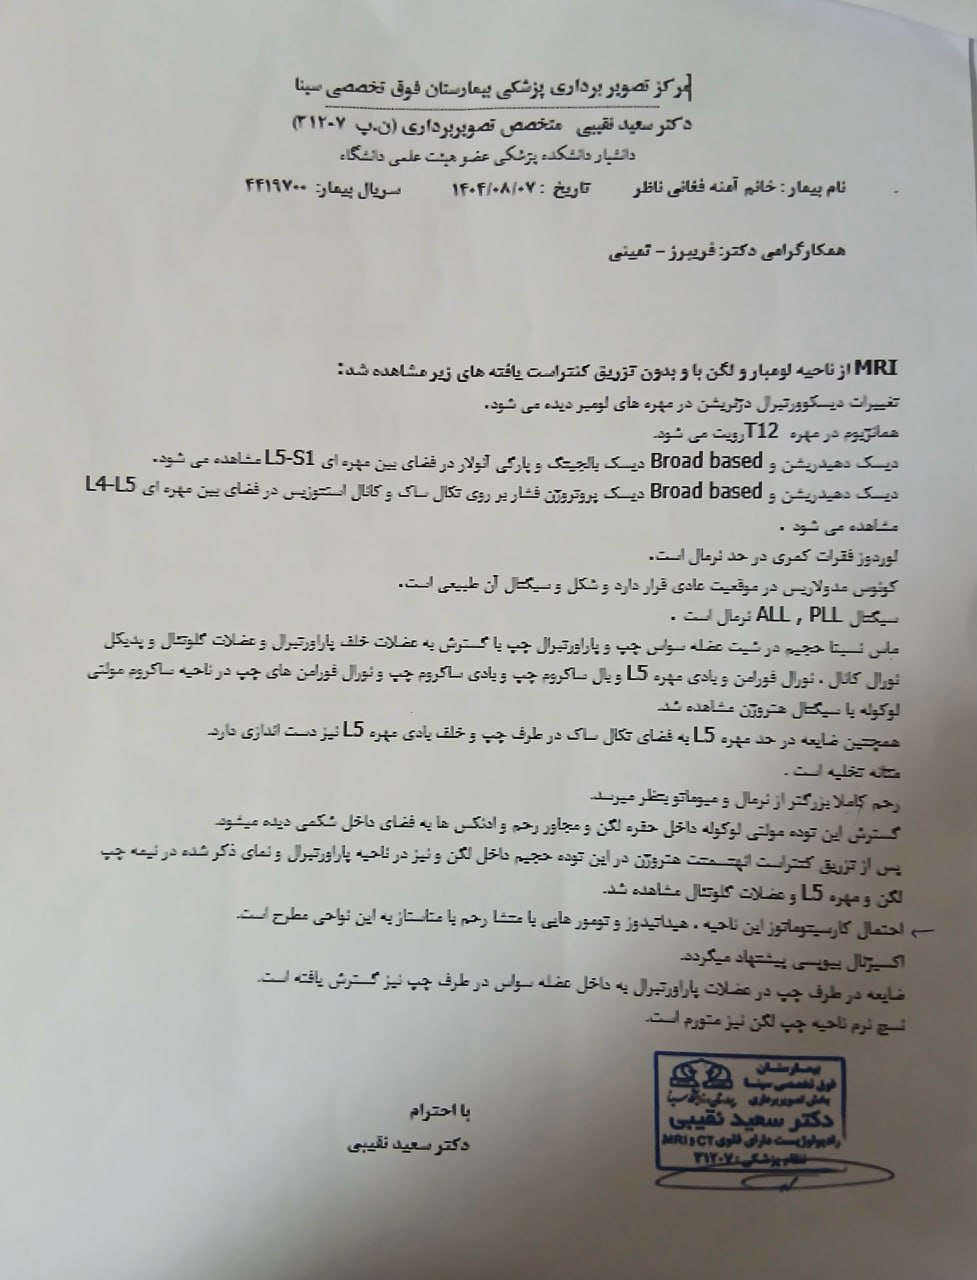

در بررسیهای تصویربرداری (MRI)،در تاریخ 24.7 ، تودهای با تشخیص کندروسارکوما همراه با DVT گزارش شده است. بیمار سابقه درد لگن داشته که شدت آن در حال حاضر نسبت به گذشته کاهش یافته است. به گفته بیمار، حجم توده در ابتدا در حدود اندازه یک تخممرغ بوده که در حال حاضر کاهش یافته است. همچنین تورم اندام تحتانی در حال حاضر نسبت به قبل کمتر شده است.

مراجعه کرده است. پس از بررسی های انجام شده در MRI انجام شده توده با درگیری مفصل ساکروایلیاک چپ و DVT؛ ابتدا تحت درمان DVT قرار گرفته است و سپس جهت پیگیری تومور رویت شده تحت بیوپسی قرار گرفته است و با تشخیص کندروسارکوما به این مرکز مراجعه کرده است و تحت کموتراپی و رادیوتراپی قرار گرفته و سایز تومور کاهش یافته است.

(تصویر مربوط به این مراجعه نیست) Other: